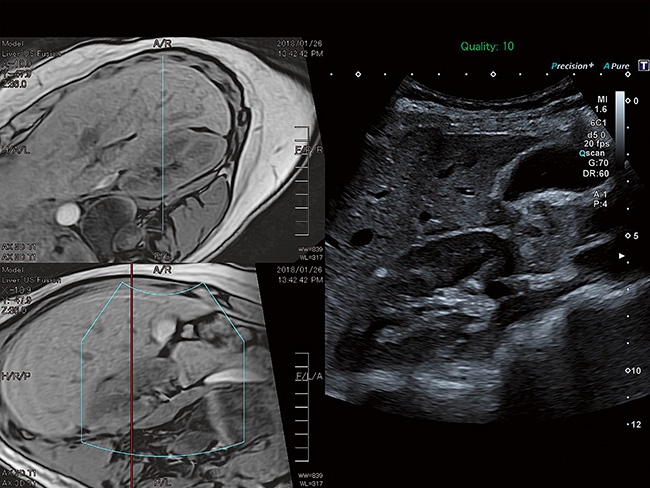

Aplio a550 может работать с линейным матричным датчиком и поддерживает новейшие монокристаллические датчики. Также Aplio a550 поддерживает большое количество дополнительных опций, таких как - SMI, Компрессионная эластография, Эластография сдвижной волны, Smart Fusion, исследования с использованием контраста (CEUS), 3D реконструкции в реальном времени (4D), функции автоматической оценки подвижности миокарда и фракции выброса.

IFusion: